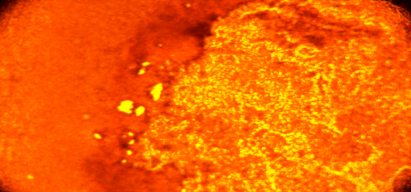

應用:用于細胞和組織缺氧的免疫化學檢測,包括免疫熒光、免疫過氧化酶或流式細胞術。該Hypoxyprobe-1 RED PE試劑盒在福爾馬林固定的石蠟包埋大鼠腫瘤組織中提供強烈的免疫染色效果,背景極低。

b. 一個小瓶(100 mg和200 mg試劑盒)或兩個小瓶(1000 mg試劑盒)含有200 ?L稀釋的RED PE染料偶聯(lián)的IgG1大鼠單克隆抗匹莫噻唑抗體(克隆11.23.22.R)。每個小瓶包含200微升的0.50 mg/ml RED PE染料-MAb1溶液,PBS中含有1% BSA和0.09%疊氮化鈉。RED PE染料-MAb1的最佳稀釋度由研究人員確定,但發(fā)現(xiàn)1:50-100的稀釋度在大鼠腫瘤組織中提供強烈的免疫熒光染色。RED PE染料-MAb1專為免疫熒光設計,可在熒光顯微鏡下或流式細胞術和Western Blot應用中可視化。免疫熒光中抗體的稀釋度通常低于免疫過氧化酶檢測系統(tǒng)中使用的稀釋度。